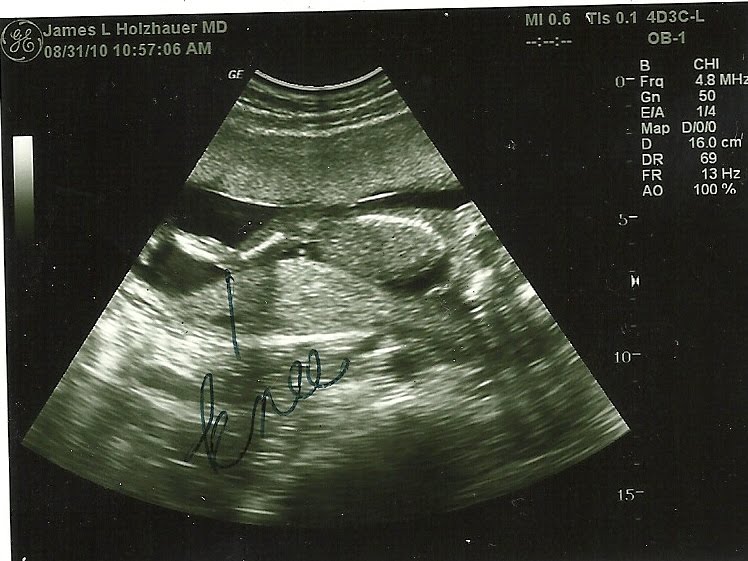

It's a Girl!!! Praise God!!

Then I had to drink some icky 50 grams of glucose drink and then the doctor came in and did an ultrasound. I was certain it was going to be a boy! But nope...there she was...Doc pointed out her little girly bump and said he was absolutely certain. (He has been doing this for over 30 years!).

Her heart was 152bpm, her legs were stretched out, and she must have been sleeping because all I saw her do was twitch her leg a little and move her foot.